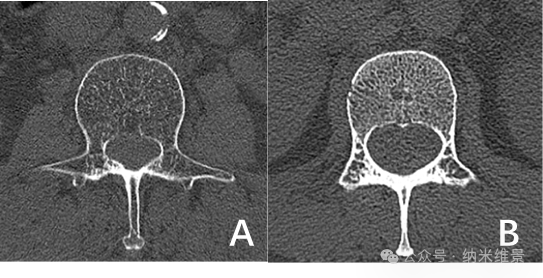

A.老年骨质疏松患者相控阵CT图 B.骨量正常的健康志愿者相控阵CT图

研究团队对100例受试者(老年组33例/中青年组67例)腰椎进行扫描,多项骨微结构指标变化显示:老年骨质疏松患者的骨小梁体积骨密度较中青年组显著下降,骨小梁连接密度有所减少。这种传统CT因分辨率不足难以清晰辨别的区域特异性差异,现可通过相控阵CT清晰呈现。

苏州大学附属第一医院与纳米维景的联合研究带来突破:相控阵CT凭借"光学旋转"技术,解决了传统CT依赖机械旋转导致的拖尾效应,将空间分辨率大幅提升,能够清晰地观测骨微结构,可精准识别骨质疏松早期的骨小梁改变,显著提高骨折风险预警准确性。